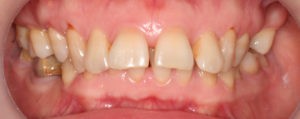

Пациентка, 43 года обратилась в клинику с жалобами на наличие промежутков между зубами, измененный наклон передних зубов верхней челюсти, появившейся за последнее время. Также пациентку беспокоил изменившийся профиль лица.